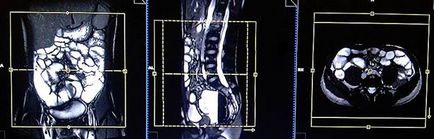

Tervezés koszorúér szeletek axiális síkban; blokk helye keresztirányban hasüregben, amint az ábrán látható. Ellenőrizze a helyét a blokk a 2 másik síkon. Ezek között a szakaszok, hogy teljesen befedje a teljes hasüreget elölről hátrafelé hasfal. A látómező (FOV) elegendőnek kell lennie, hogy fedezze a has és a medence a gyomor, hogy a szint a fancsonti. Annak megakadályozása érdekében műtermékek GDV kell használni fázist túlmintavételezésre (túlmintavételezés). Fontos, hogy a beteget a levegőt-hold alatt képrögzítő csomagokat. (A mi osztály, azt utasítják a pácienseket be és ki kétszer, mielőtt „be és tartsa vissza a lélegzetét” elején a scan).

Tervezés tengelyirányú szeleteket a koszorúér síkban; blokk helye keresztirányban hasüregben, amint az ábrán látható. Ellenőrizze a helyét a blokk a 2 másik síkon. Ezek a szakaszok teljes mértékben meg kell terjednie a teljes hasüreget és a medence a gyomorból az a szint, a fancsonti. Annak megakadályozása érdekében műtermékek GDV kell használni fázist túlmintavételezésre (túlmintavételezés). Tájékoztassa a beteget, hogy lélegzet-visszatartás során képrögzítő csomagokat. (A mi osztály, azt utasítják a pácienseket be és ki kétszer, mielőtt „be és tartsa vissza a lélegzetét” elején a scan).